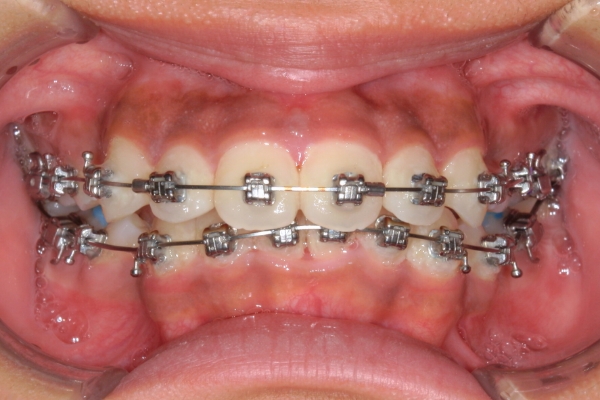

PROCESS

半年

上顎前歯が1cm近く前方に出ており、叢生を改善しつつ前歯を大きく引っ込めるために上下顎小臼歯の抜歯が必要と診断しました。治療後は、主訴であった前歯の突出と奥歯の噛み合わせのずれが改善され、上下の咬合関係が安定しました。